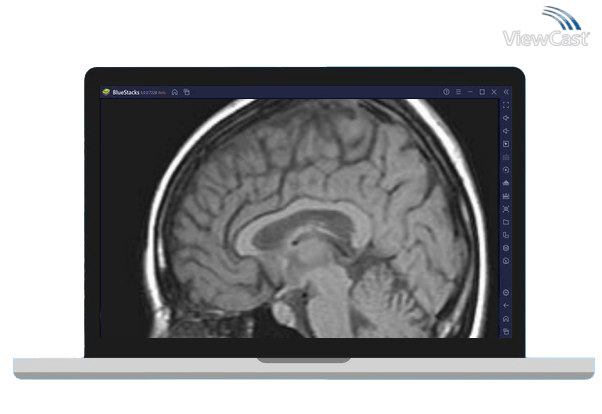

MRI Viewer is primarily a mobile app designed for smartphones. However, you can run MRI Viewer on your computer using an Android emulator. An Android emulator allows you to run Android apps on your PC. Here's how to install MRI Viewer on your PC using Android emuator:

You can now use MRI Viewer on your PC within the Anroid emulator. Keep in mind that it will look and feel like the mobile app, so you'll navigate using a mouse and keyboard.